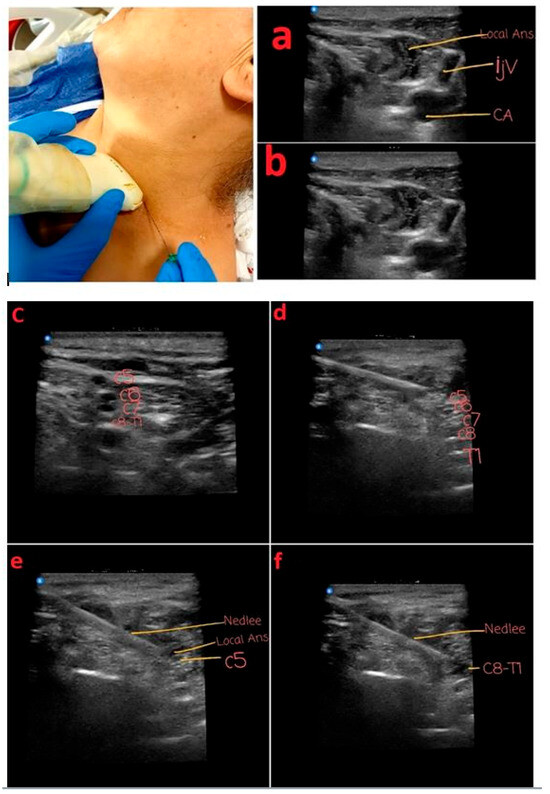

4. Anesthesia Preparation